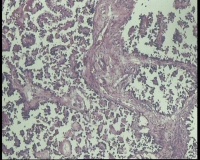

| 性别 | 女 | 年龄 | 53岁 | 临床诊断 | 右侧卵巢囊肿 |

| 一般病史 | 彩超:盆腔可见囊实性回声,囊性为主,大小约5.0x3.7厘米,其内可见分隔回声,部分分隔内回声不纯净,形态欠规整 | ||||

| 标本名称 | 腔镜下右侧卵巢囊肿手术 | ||||

| 大体所见 | 囊壁样组织5.5x5.0厘米,4.5x2.5厘米2块,壁厚0.1-0.2lm,囊壁大部分光滑,局灶见0.7x0.5x0.3厘米淡黄色突起组织,另见淡黄色、肉粉色质软组织2.8厘米一堆。 | ||||